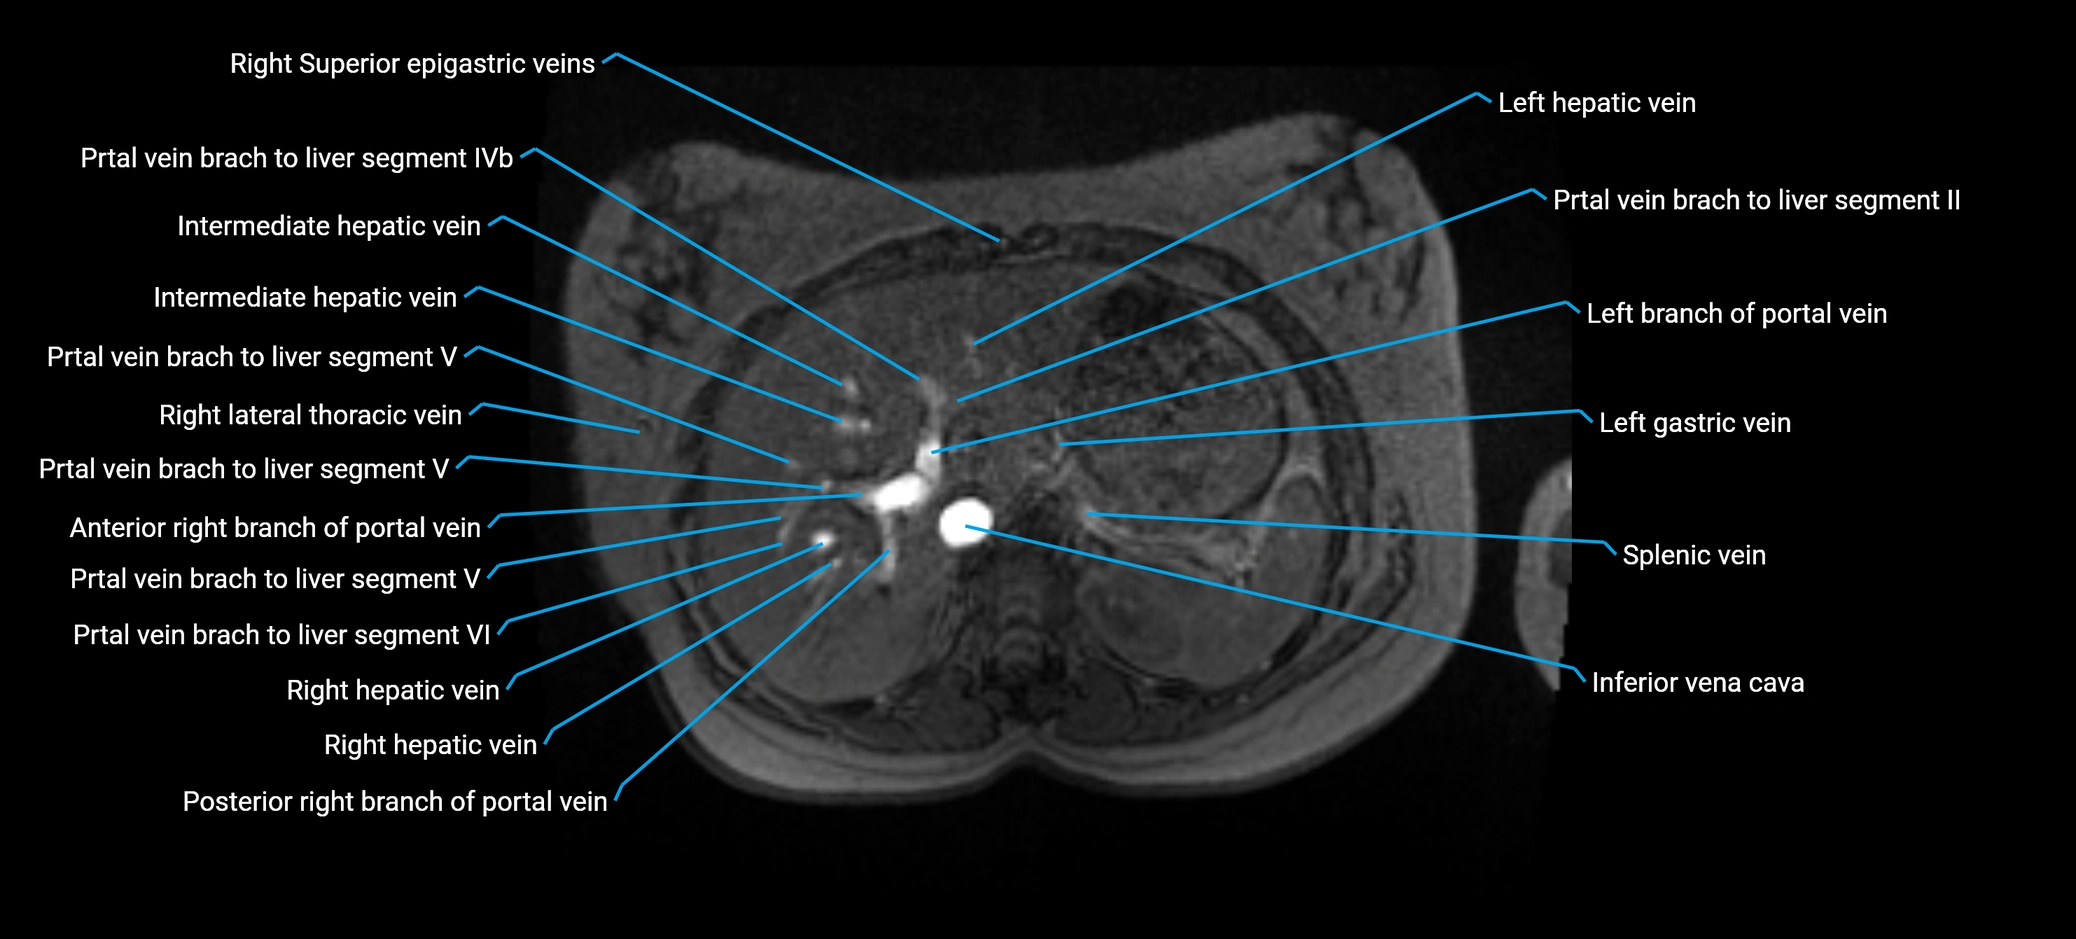

The anterior right branch of the portal vein is a major intrahepatic division of the right portal vein. After the main portal vein bifurcates into right and left branches, the right portal vein divides into anterior and posterior segmental branches.

The anterior right branch supplies the anterolateral liver segments (Segment V) and anteromedial liver segments (Segment VIII) within the right hepatic lobe. It operates as a key vascular route delivering nutrient-rich portal venous blood to the central and superior right liver.

MRI image

image